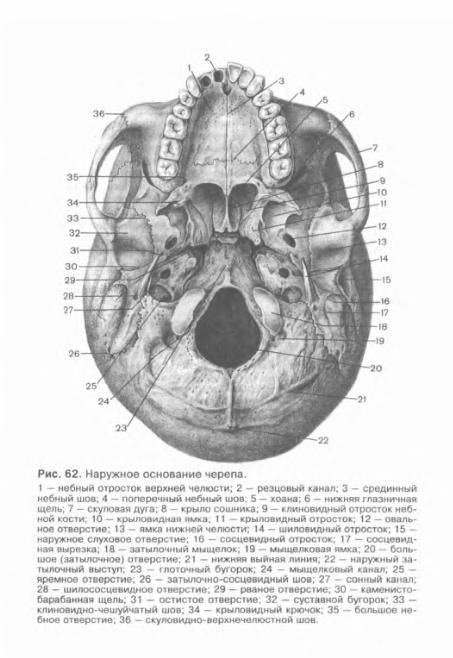

Анатомические детали: Фотографии топографии черепа с нижнего вида

Раздел: Альбом идей